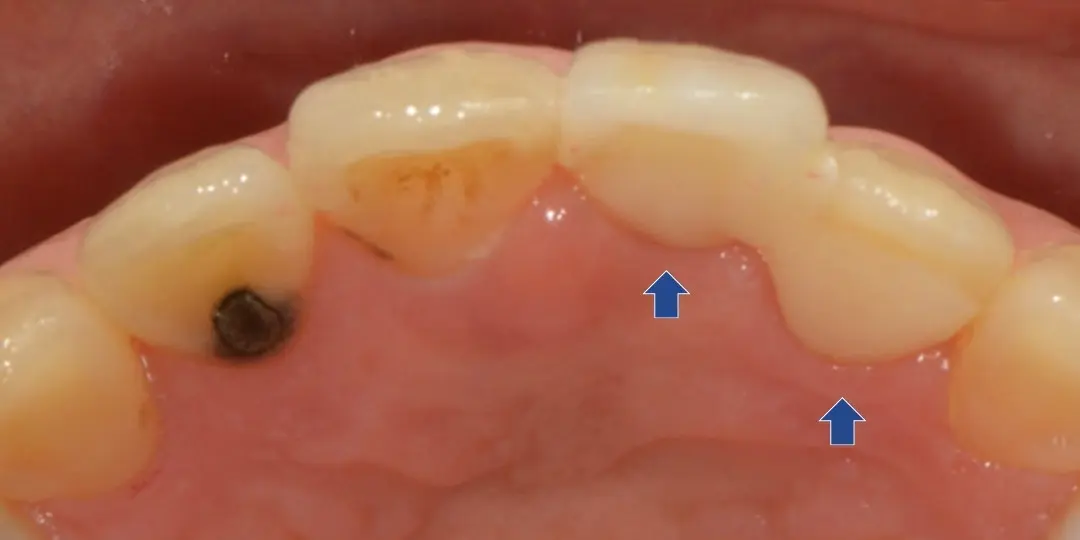

インプラント・ブリッジ・入れ歯の治療計画をお話しさせていただき、治療期間やリスク、審美性や周囲の歯への負担を考慮して、接着性ブリッジで修復しました。

接着性ブリッジとは、隣の歯の一部のみを削り、貼り付けるタイプの補綴物です。

支台歯の削る量を最小限に済ませ、審美性も高いのが特徴です。

抜歯した状態。治療期間中は仮歯を入れます。

隣の歯の一部のみを削り、ジルコニアを貼り付けています。削る量が少なく負担の少ない治療です。